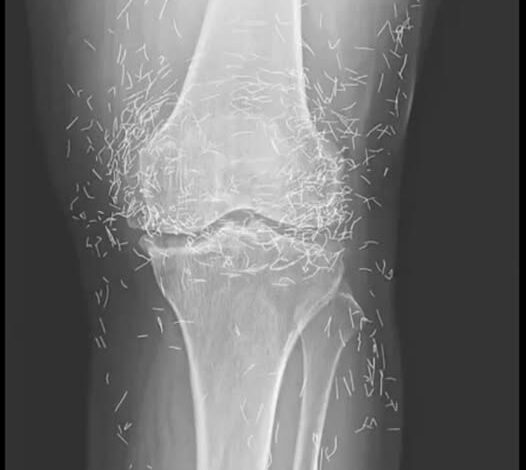

Doctors find “gold mine” in woman’s knees

When a 65-year-old South Korean woman went in for knee pain, doctors weren’t expecting to strike gold. But that’s exactly what they found.

Acupuncture, a centuries-old alternative treatment, involves inserting needles into the body at specific points to relieve pain or treat illnesses. In this case, the needles— presumably made of gold — were intentionally left in her knees for continued stimulation.

He also warned that embedded needles can complicate X-ray readings. “The needles may obscure some of the anatomy,” Guermazi said in 2013.